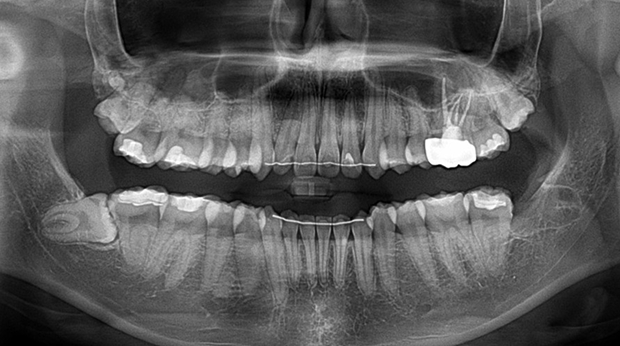

임플란트와 사랑니 발치는 외과적 시술로 잇몸을 절개하는 외과적 시술은

짧으면 짧을 수록 시술 후 붓기와 통증이 최소화됩니다.

치과의사 경력 14년차 구강외과 전문의가 빠르고 안전하게, 아프지 않게 수술해 드립니다.

치과경력 14년차 구강외과 전문의